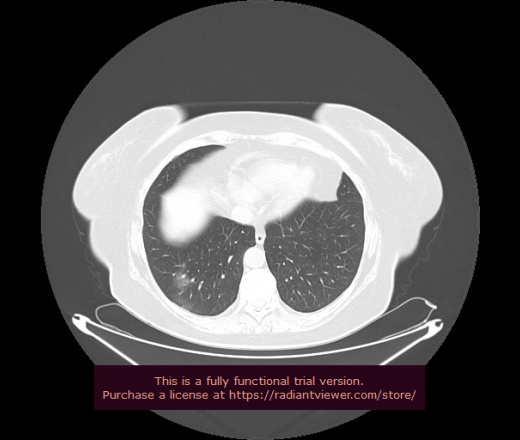

Уважаемые коллеги, если имеется интерес, сможете ли Вы спрогнозировать дальнейшее +-одинаковое течение процесса у 4 данных разных пациентов? Зацепиться где-то можно очень просто, где-то нельзя.